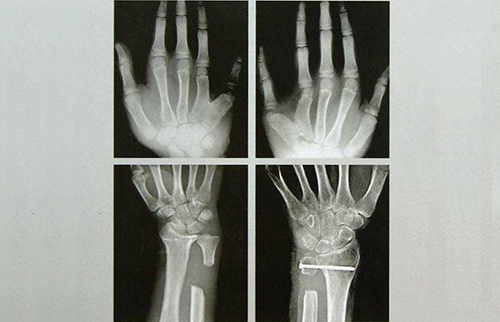

手足外科